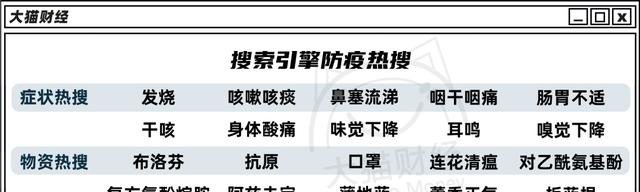

不过,“水泥封鼻子,刀片拉嗓子”,显然都是小事情,越来越多的关联症状频繁上了热搜,“沉默性缺氧”、“病毒性心肌炎”、“白肺”才是最令人闻风丧胆的。

一线医生说,目前的呼吸科基本上全是肺炎患者,“真正的肺炎,磨玻璃,白肺”。

啥是白肺呢?

“白肺”全称为急性呼吸窘迫综合征(ARDS),一般指的是重症肺炎患者在X光或CT检查下,肺部显影呈一大片白色状而得名。

“沉默性缺氧”侵蚀老年人,“白肺”已经开始侵蚀青少年,均与呼吸相关,于是,新的财富密码又出现了,血氧仪和制氧机开始大卖。